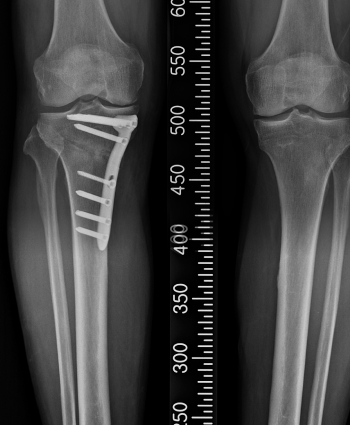

X-ray 관절 간격, 관절 정렬, 뼈 변화 확인

휜다리교정술 (절골술)

무게 중심을 바꿔 관절염 진행 지연

인공관절치환술 (TKR)

손상된 관절 제거 후 인공관절 삽입, 보행 기능 회복